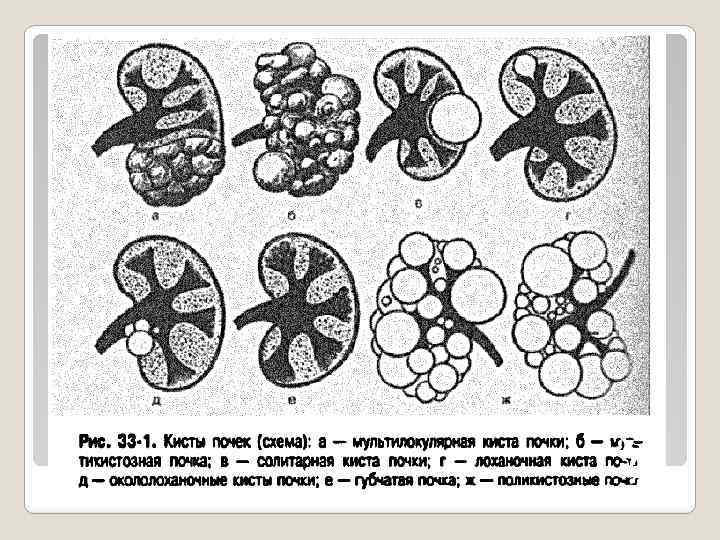

Аномалии развития почек Количества: • Агенезия • Гипоплазия • Аплазия • Добавочная почка • Удвоение почки Взаимоотношения: • Симметричные: -подковообразная -галетообразная • Асимметричные: -I-S-L –образная почка Положения: Дистопия Эктопия § Гомолоатеральная § Высокая: внутригрудная торакальная § Низкая: - поясничная - подвздошная - тазовая § Гетеролатеральная (перекрестная): - S-L-образная - Двусторонняя - Со сращением - Без сращения Структуры: • Кистозные аномалии: -поликистоз -губчатая почка -мультикистозная дисплазия • Мультилокулярна я киста • Солитарная киста • Лоханочная киста • Окололоханочная киста • Дермоидная киста

Аномалии развития почек Количества: • Агенезия • Гипоплазия • Аплазия • Добавочная почка • Удвоение почки Взаимоотношения: • Симметричные: -подковообразная -галетообразная • Асимметричные: -I-S-L –образная почка Положения: Дистопия Эктопия § Гомолоатеральная § Высокая: внутригрудная торакальная § Низкая: - поясничная - подвздошная - тазовая § Гетеролатеральная (перекрестная): - S-L-образная - Двусторонняя - Со сращением - Без сращения Структуры: • Кистозные аномалии: -поликистоз -губчатая почка -мультикистозная дисплазия • Мультилокулярна я киста • Солитарная киста • Лоханочная киста • Окололоханочная киста • Дермоидная киста

Кистозные аномалии почек

Кистозные аномалии почек